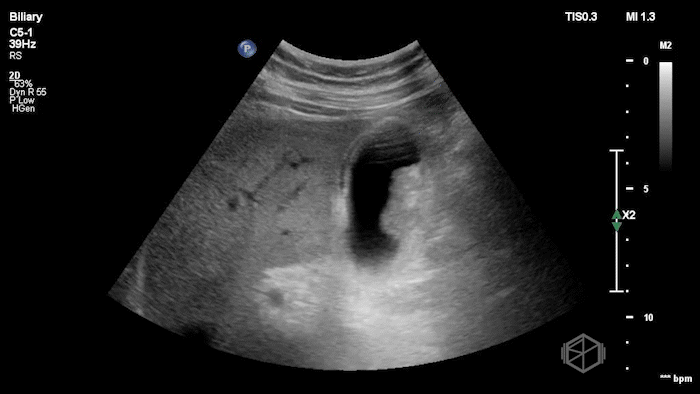

Their POCUS is below:

The POCUS demonstrated a thickened, edematous gallbladder wall with tumefactive sludge and gallstones, concerning for acute cholecystitis, though an underlying mass could not be excluded. A CT scan was obtained, which showed a layering gallstone versus gallbladder polyp, gallbladder wall edema, and possible pericholecystic fluid.

Surgery was consulted and recommended a radiology ultrasound, which predictably reported findings similar to the initial POCUS examination: gallbladder neoplasm versus tumefactive sludge versus non-calcified gallstones, with gallbladder wall edema concerning for acute cholecystitis. The radiology read recommended further evaluation with MRCP, which ultimately demonstrated findings consistent with acute cholecystitis without evidence of malignancy.

Diagnosis: Acute cholecystitis, tumefactive sludge